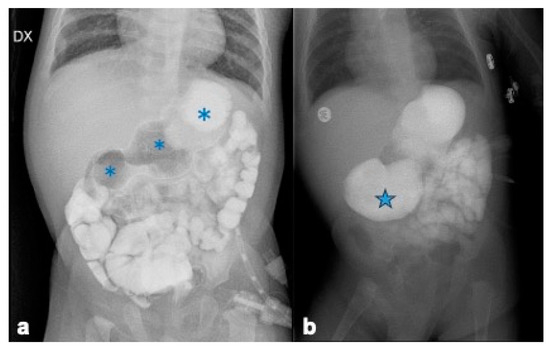

2.3. Investigations